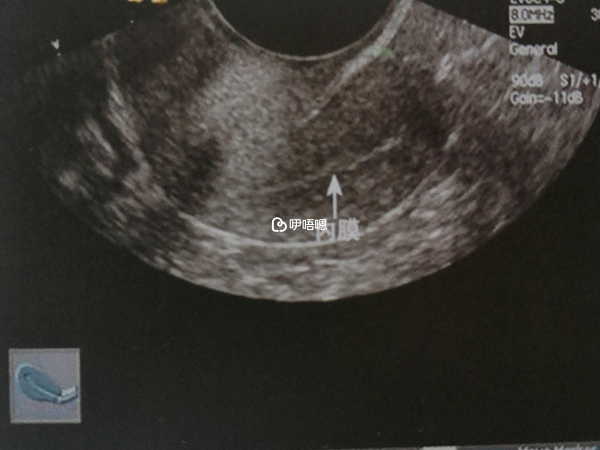

幼稚子宮屬於一種先天發育不全的問題,檢查時可以看到宮頸呈現錐形,其中宮體與宮頸的比例是1∶1,子宮比較小,常常會表現為月經失調,月經量特別少。這種疾病可以通過科學的方法進行治療。如果治療效果不好,可能會影響女性的生育。

在青春期之後可以服用雌激素和孕激素進行相對的序貫治療,這種治療方法可以促進子宮發育。即使子宮是在胚胎髮育期間雙側的副中腎管在匯合之後不久就停止發育了,這種情況通常合併無陰道症,子宮極小,約1-3釐米,並且沒有宮腔和內膜。如果確定子宮沒有宮腔和內膜,即便是利用雌孕激素來進行治療也很難再長出來,也就不會有生育的功能,所以幼稚子宮的最佳治療時期是12-14歲之間,且在此期間越早治療效果越好。

手術治療幼稚子宮一般採用宮腔擴大術:利用宮腔鏡和腹腔鏡聯合對宮腔進行擴大術,術後使用帶有生物防粘膜的特製支撐物,一個月後再次進行手術,直至宮腔能夠容納5ml液體後即可。